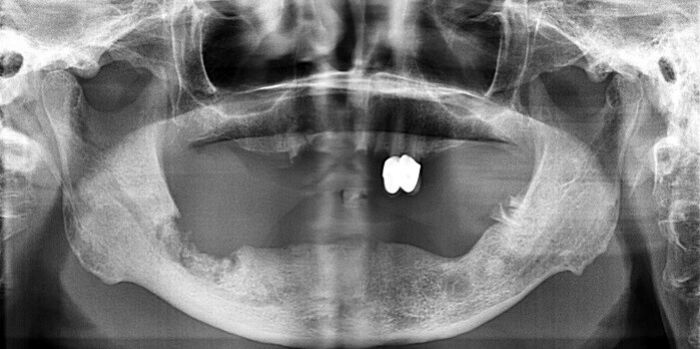

70.依據附圖X光片,最不可能的診斷為何?(A)osteoporosis(B)osteomyelitis(C)osteoradionecrosis(D)medication-related osteonecrosis(MRONJ)